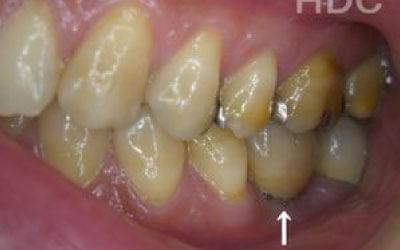

最も大きな違いは、前後の歯の寿命に影響が出ることです。

ブリッジの場合、抜けた部分の前後の歯を大きな虫歯と同じくらい削る必要があります。

また、抜けた歯の力を前後の歯が支えているため、ブリッジを支える歯には常に1.5倍の負担がかかることになります。

1)ブリッジ

2)歯を大きく削る+支えの歯に1.5倍の力がかかる

3)前後の歯の寿命が著しく減る

ブリッジの支えの歯は、データでは10年以内に68%が抜歯になります。